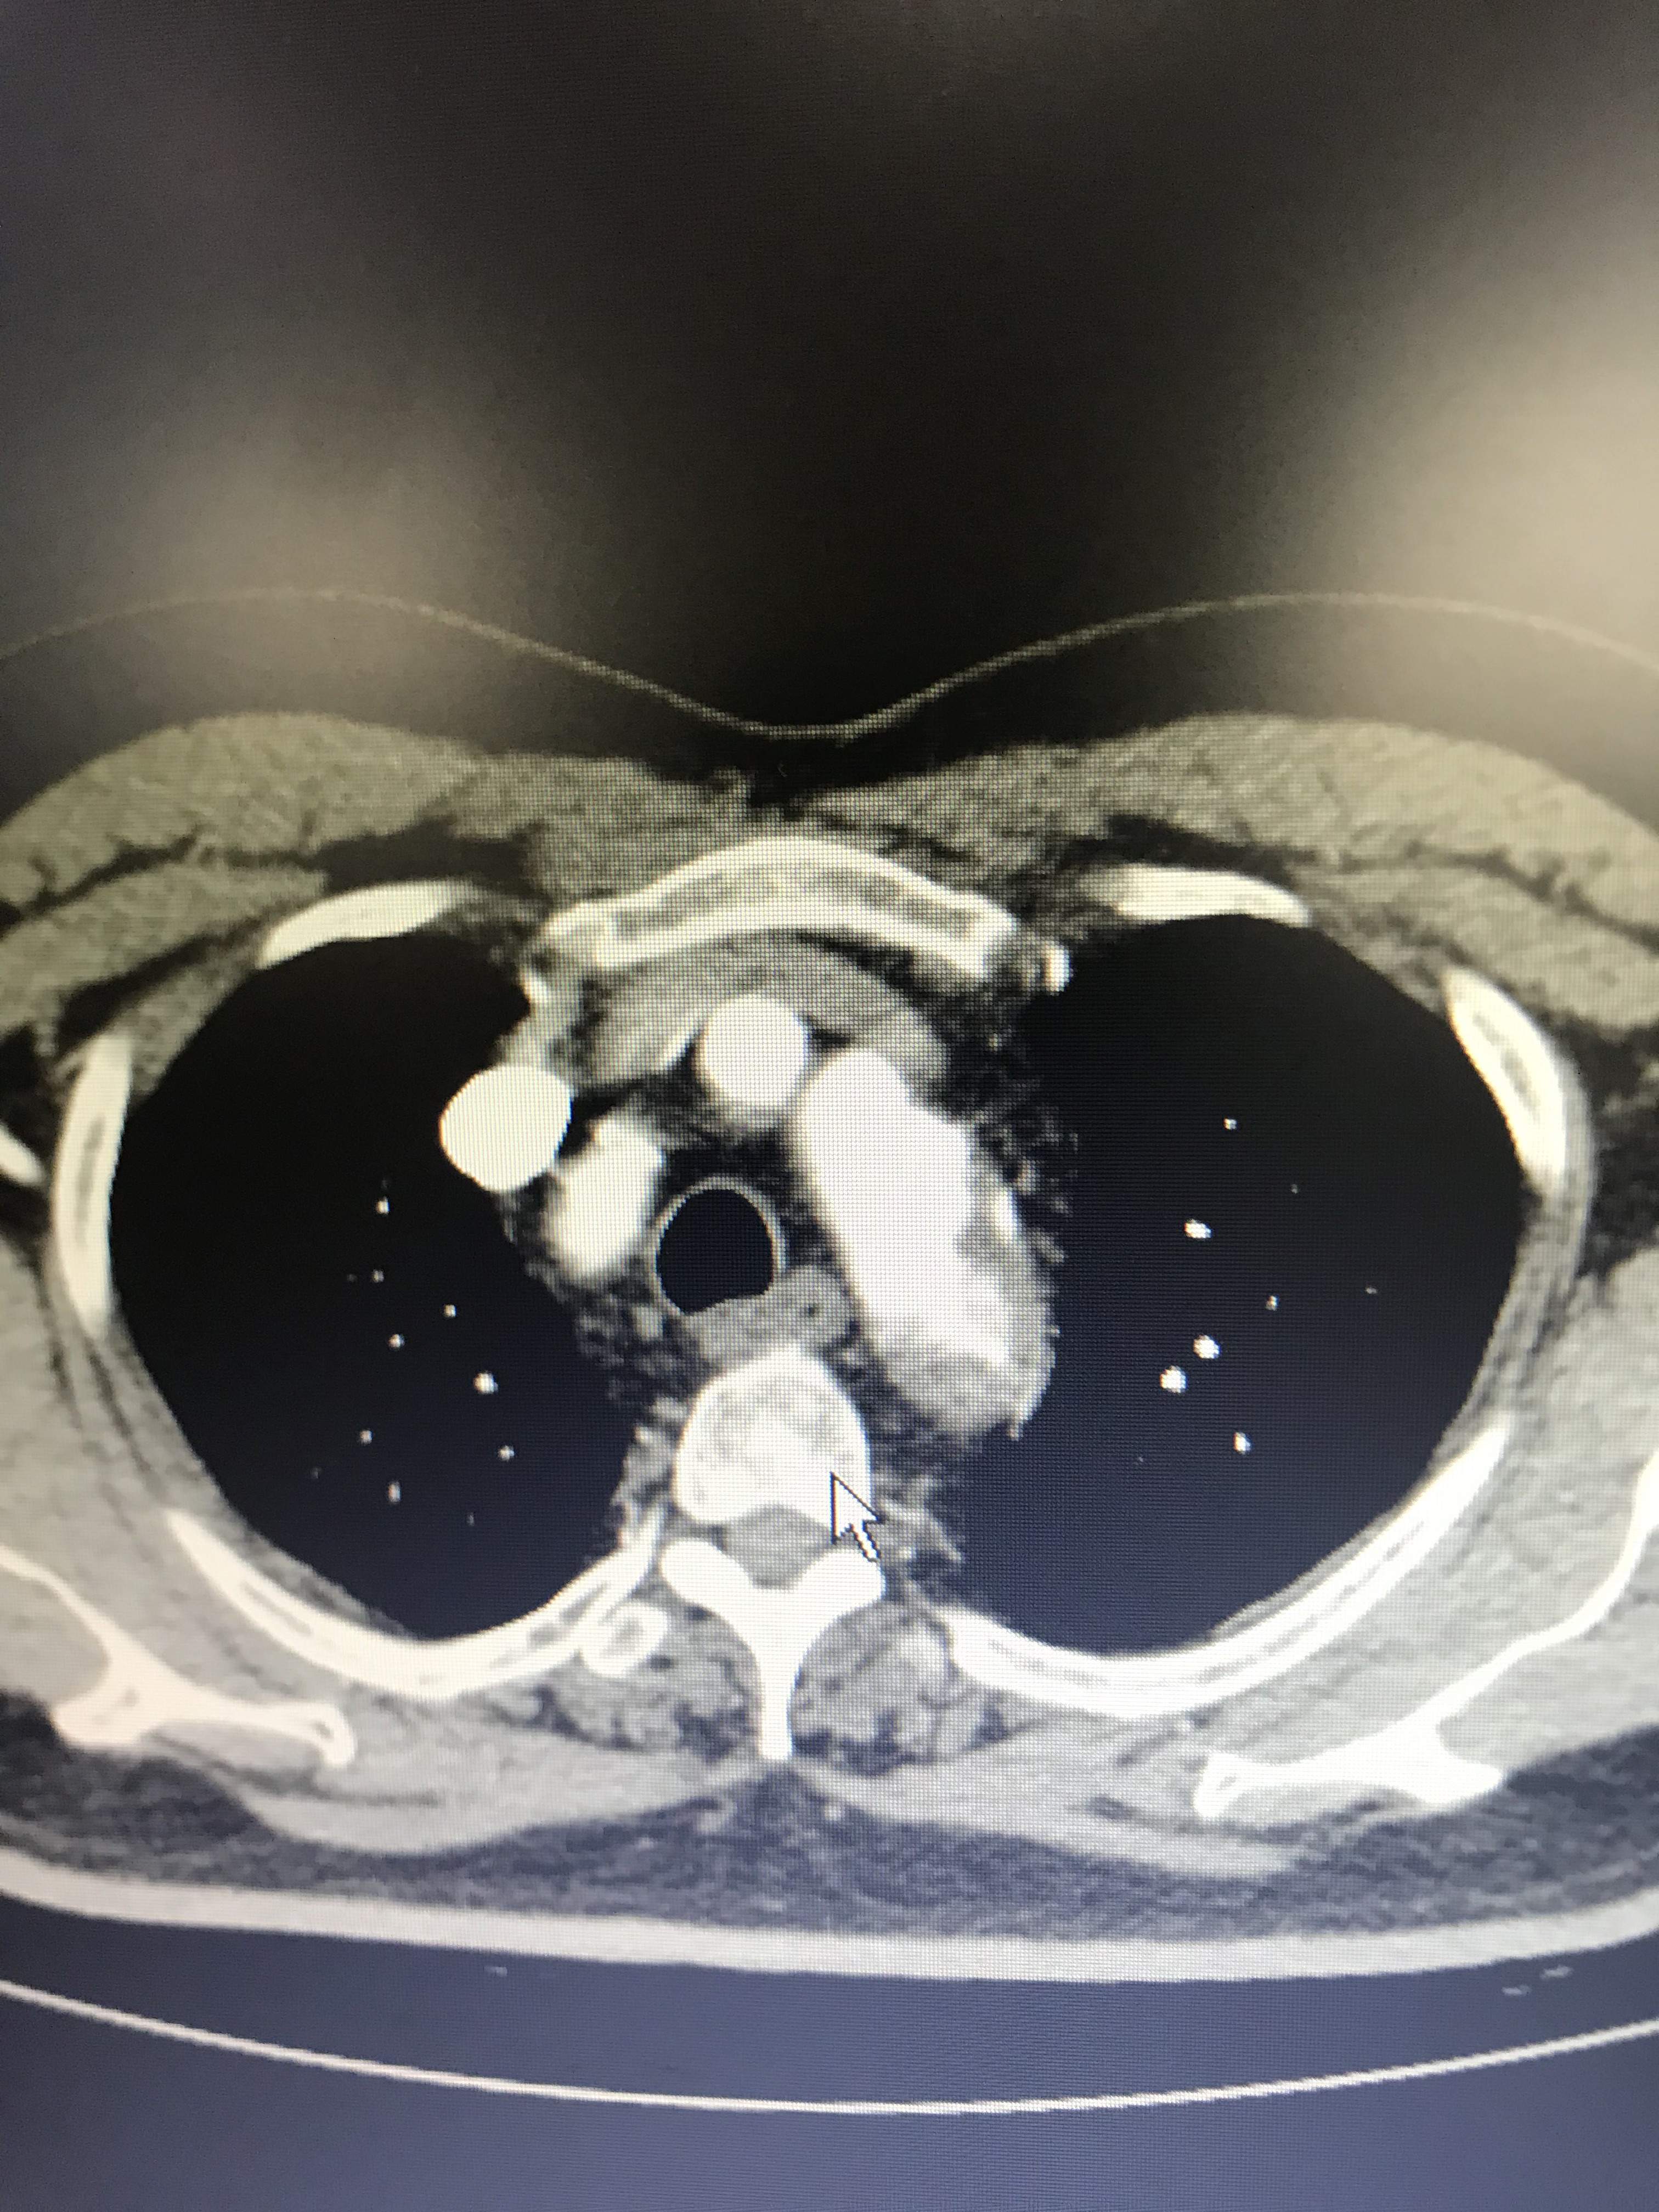

病人胸痛,这图像竟然不是主动脉溃疡?

大家帮我忙看看,到底是不是主动脉溃疡?